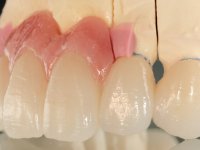

Alginate impressions were made at both arches arcades, accompanied by intermaxillary registration relations and collecting information with facial bow facial bow. In the laboratory, a provisional bridge with 13 elements in autopolymerizable acrylic was built, in which a metallic reinforcement was included. Teeth 1.7 / 1.4 / 1.3 / 2.2 / 2.3 / 2.4 and 2.6 were used as pillars. The metal-ceramic bridge was removed after performing longitudinal cuts with diamond burs. The dental abutments were reprepared and the temporary bridge was relined in the mouth with self-curing acrylic. After confection of the provisional bridge, a gingival epithesis was made using composite resin with gingival tonality in order to function as a mock-up, which allowed the patient to preview the possibility of using gingiva shade ceramics in the final work. This option was approved by the patient. Subsequently, the placement of two implants in the first quadrant was planned and executed. The provisional monoblock was removed for placement of the implants, and after surgery was again cemented provisionally. After the osseointegration period, the impressions were made to the maxilla. In the anterior zone, impregnated gingival retraction cords were used, and in the posterior areas, kaolin paste was used. Implant printing utilized the open tray technique. The printing material used was soft and regular putty addition silicone, both fast-setting. In the laboratory, the model of provisional restorations and the gingiva epithesis mock-up served as orientation for waxing the infrastructure. The plaster work model and the waxing of the infrastructure were placed in a laboratory scanner and yielded a digital work model, in which the scanning of the waxed infrastructure was superimposed. This overlay facilitated the CAD design of the Zr infrastructure. Subsequently, the CAD drawing for a CAM milling process provided the Zr pieces. The infrastructure was pigmented with a pinkish coloration, which favors the subsequent placement of gum shade ceramic. During the modeling of the infrastructure, the need to increase the occlusal wear on tooth 1.4 was detected. This was done in the real working model cast and an acrylic wear control guide was created, which accompanied the proof of the infrastructures. Corrective wear and Zr parts test were performed in mouth. During the test, the color choice of the gum shade ceramic was reassessed. The treatment was finished in the laboratory, and after approval by the patient, was definitively placed in the mouth.